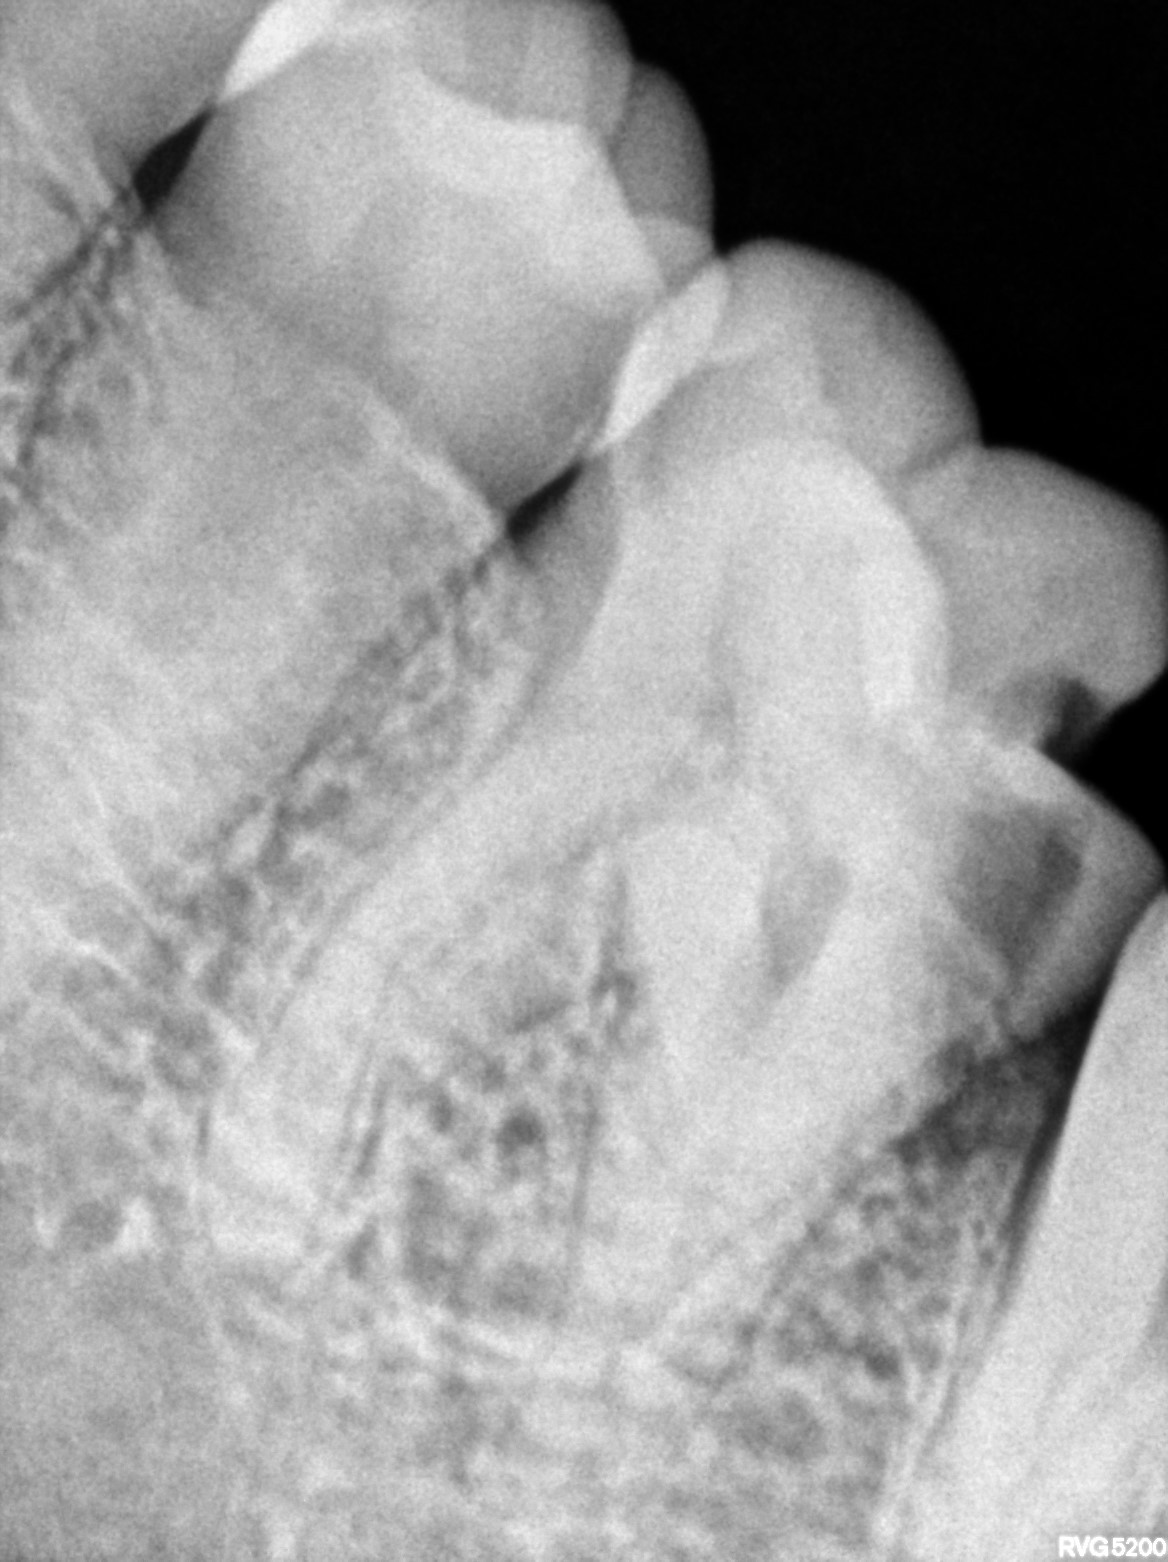

Dental Radiographs FHIR: DocumentReference · LOINC 24641-7

xray_1770998647_1.jpg

24641-7